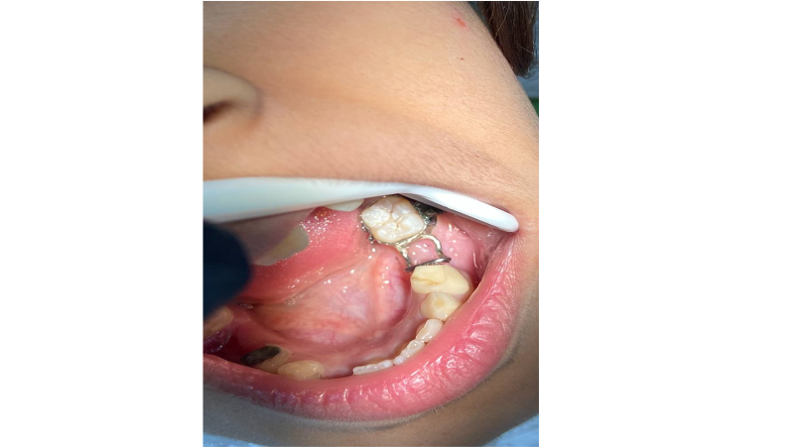

Part of the SPACE MAINTAINER work for a patient in the pediatric dental clinic.